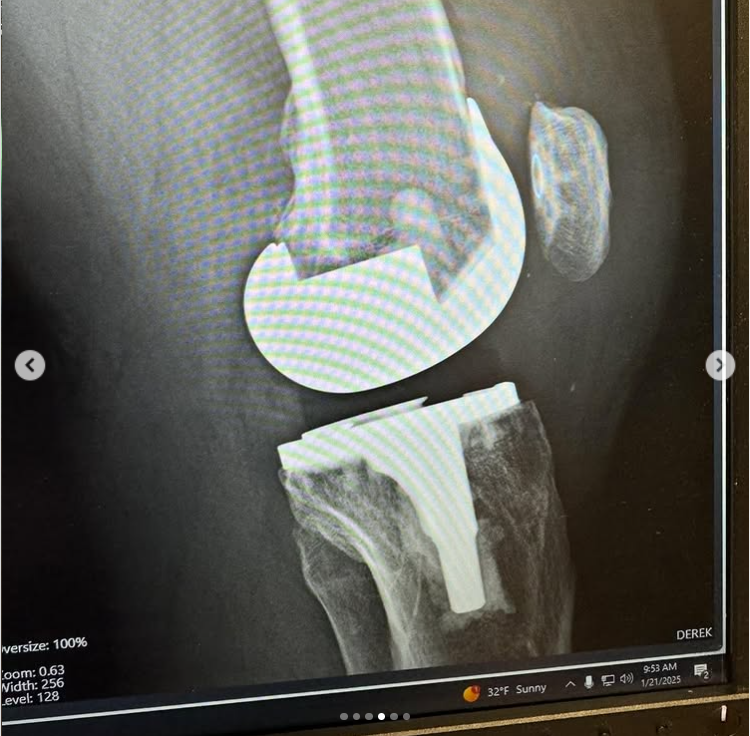

How it was. And how it is…

I am 7 weeks post op on a Total Knee Replacement. My left knee was on its last leg, and I have been putting this surgery off for years.

Post op X-Rays show everything is healing nicely.